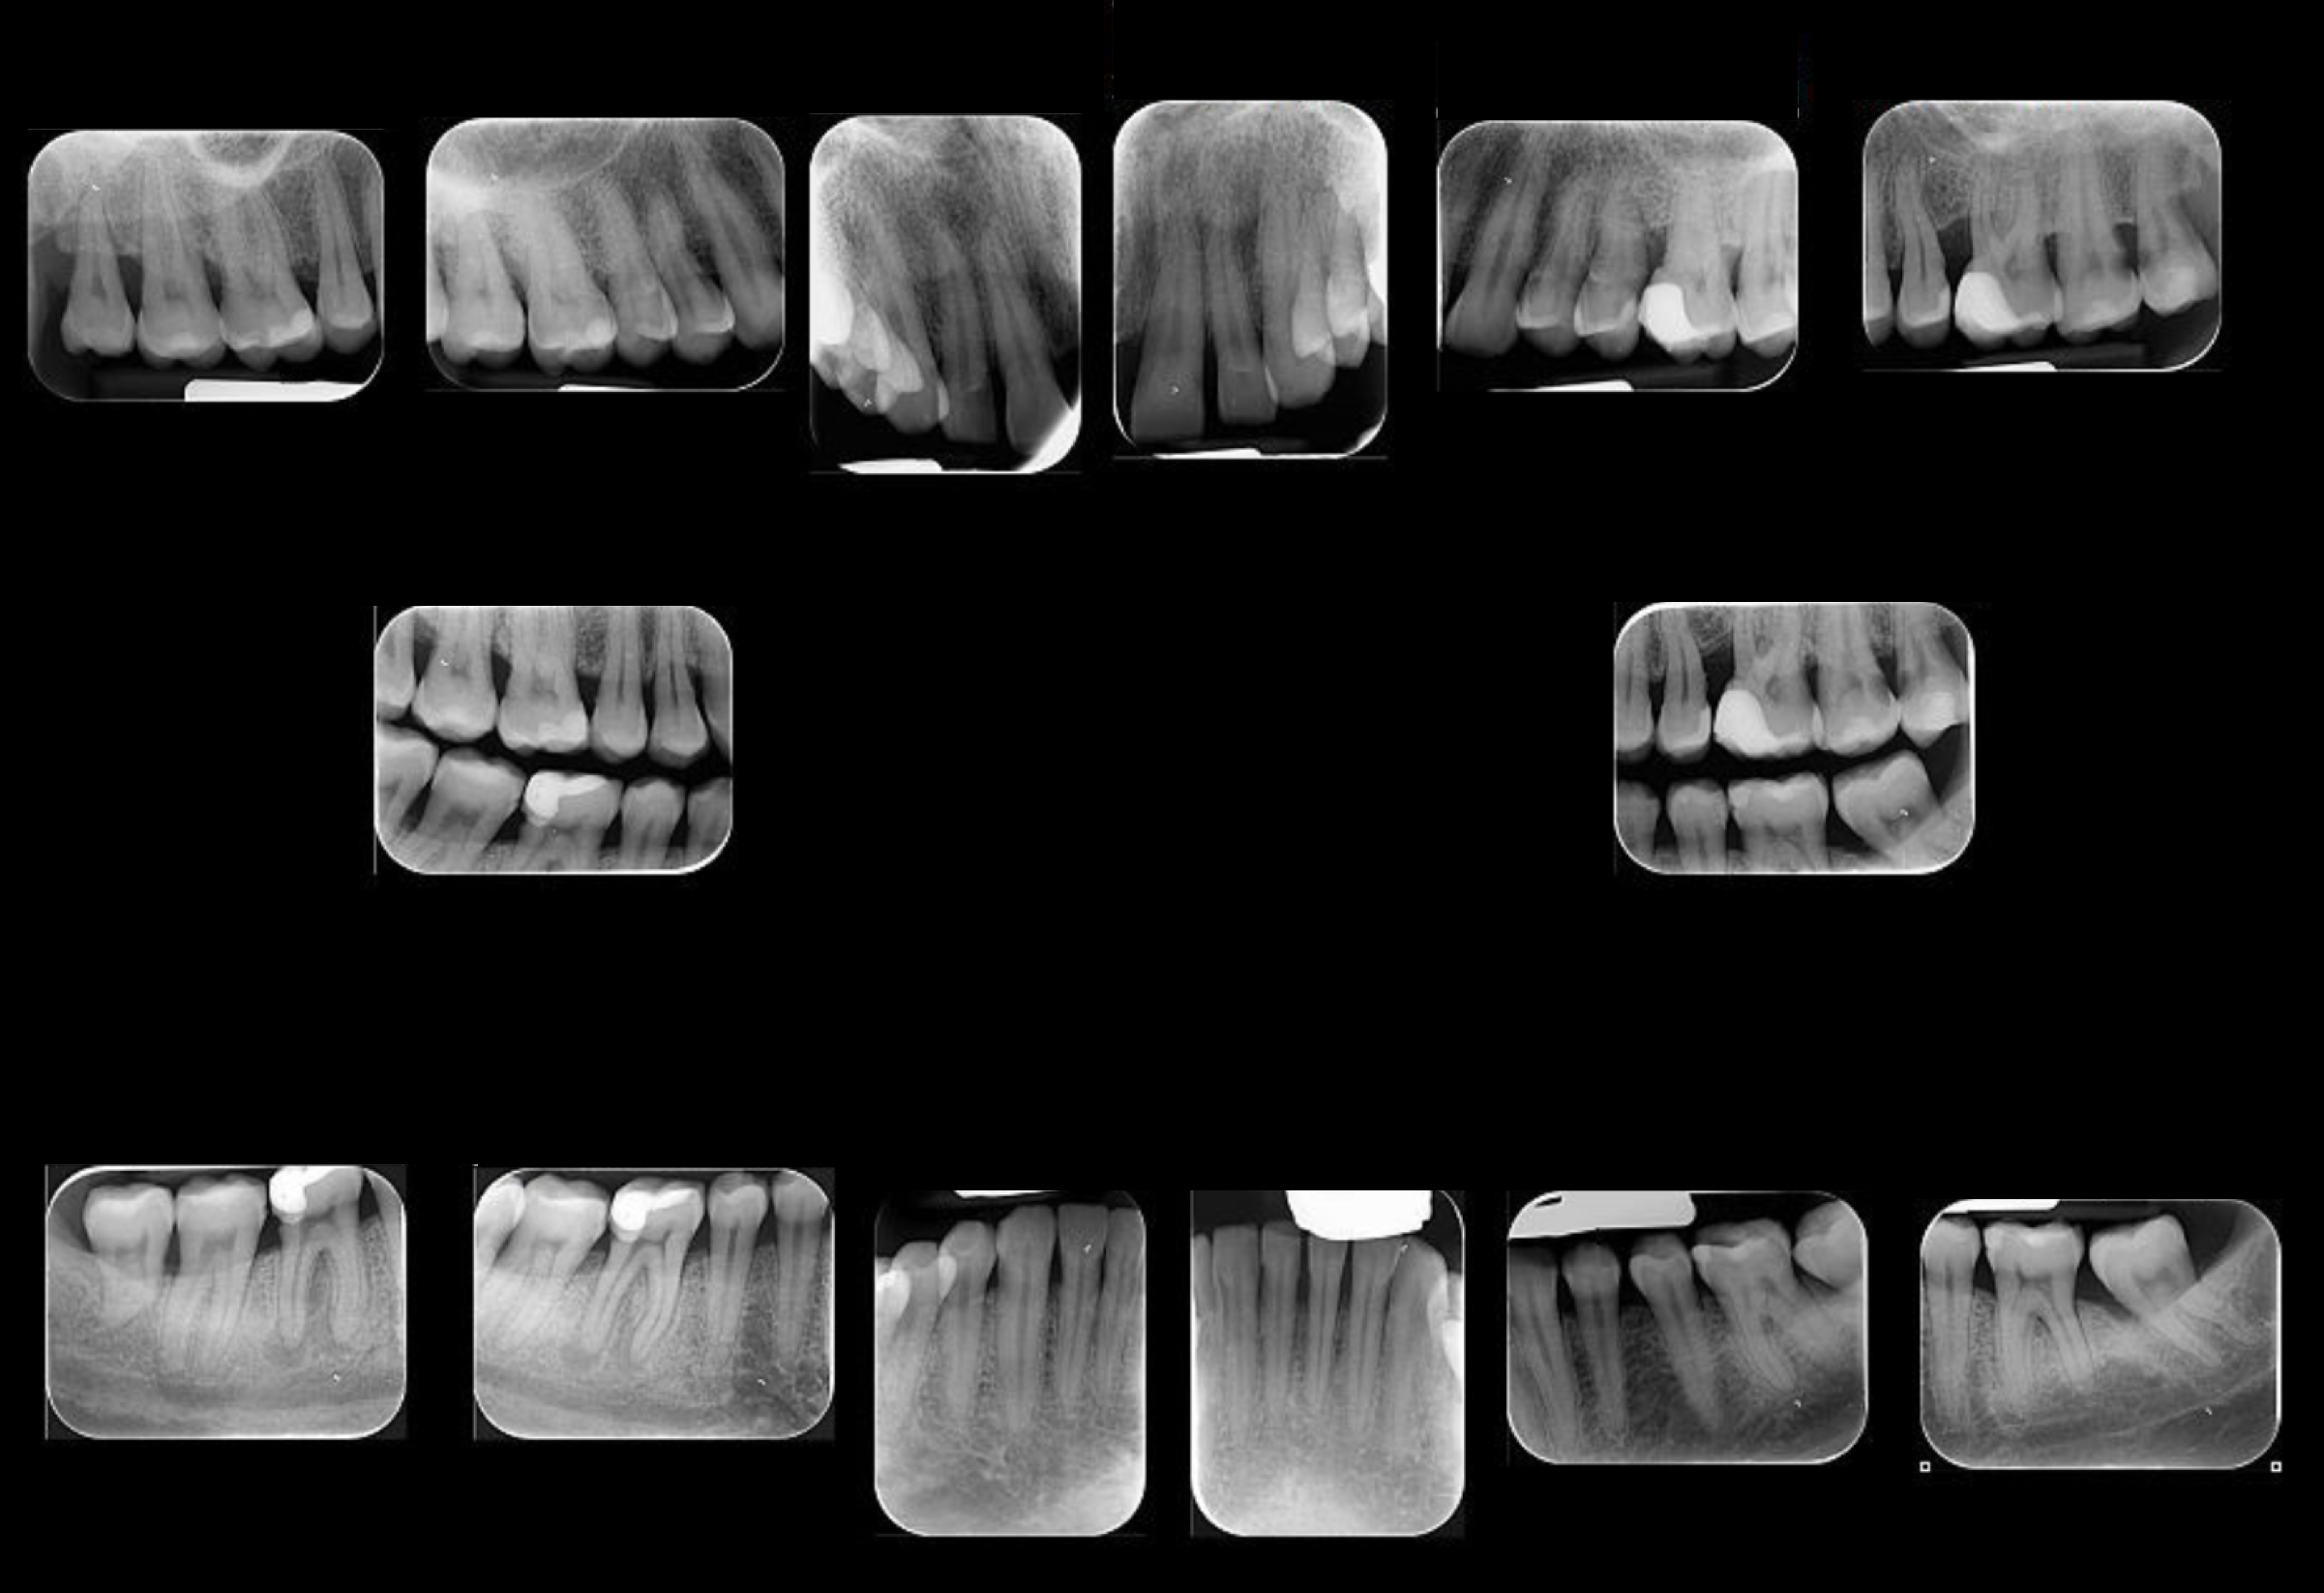

L’inquadramento diagnostico: status radiografico e sondaggio parodontale (foto in calce)

1. Status radiografico

Uno status radiografico completo (endorali periapicali o bite-wing estese) consente di:

• Valutare il livello dell’osso alveolare

• Identificare difetti verticali

• Rilevare eventuali lesioni endo-parodontali

• Analizzare incongruenze protesiche o restauri debordanti

La radiografia non serve solo a “vedere l’osso”, ma a comprendere il pattern di perdita ossea, fondamentale per stabilire lo stadio della malattia.

2. Sondaggio parodontale

Il sondaggio parodontale è l’esame clinico cardine. Si misura la profondità di sondaggio in sei punti per ogni dente, registrando:

• Profondità della tasca

• Sanguinamento al sondaggio (BOP)

• Recessioni

• Perdita di attacco clinico

• Mobilità

• Coinvolgimento delle forcazioni